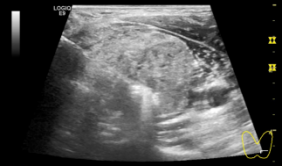

经过与患者耐心的沟通,患者决定尝试这种微创治疗方法来解决长期以来的困扰。术前患者由于对手术的未知而情绪紧张、心率加快,血压一度高达170/100mmHg,为缓解患者的紧张情绪,超声科副主任张巍多次通过手机提示患者如何配合检查与治疗,充分缓解了患者的焦虑及恐惧,最终成功完成手术。告知患者手术成功后,患者对超声科介入团队的工作表示充分的认可,并通过手语向医务人员们表示了感激之情。

图 术前及术中张巍主任多次通过手机提示患者如何配合检查与治疗